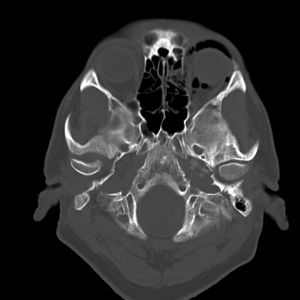

Computed Tomography: This scan is the most definitive imaging modality for diagnosing OE and helps identify the presence, location, and volume of air in the orbit (see Figure 2). It can also confirm the presence of bony defects, provide information about the optic nerve, and help visualize extraocular muscles as well for entrapment.